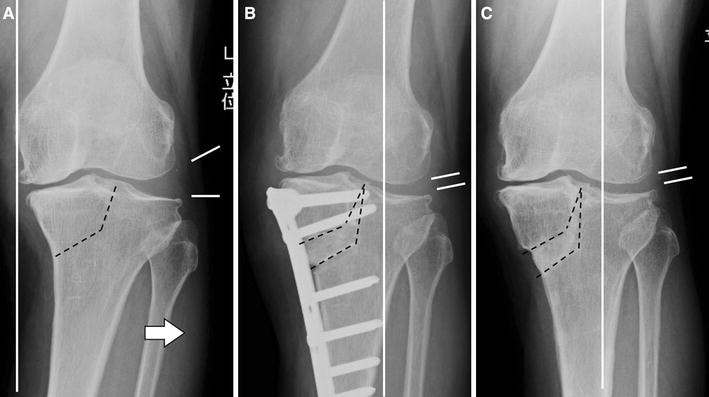

TCVO corrects knee alignment by reshaping the tibial condyle. First, surgeons perform detailed imaging, including weight-bearing X-rays and alignment studies. Next, they calculate the correction angle required to restore proper load distribution.

The surgeon makes a precise incision near the upper tibia.

The surgeon carefully performs a controlled bone cut.

The surgeon opens or reshapes the bone wedge to achieve valgus alignment.

The surgeon stabilizes the correction using advanced fixation plates.

Furthermore, surgeons ensure joint line correction to improve congruity and stability. As a result, the knee regains balanced biomechanics.

1. Preoperative Planning

Surgeons conduct comprehensive assessment including:

Clinical examination

Standing alignment X-rays

MRI if required

Cartilage evaluation

Through this evaluation, surgeons customize the surgical correction for each patient.

2. Surgical Correction

During the procedure, surgeons:

Administer regional or general anesthesia

Perform precise osteotomy

Realign the tibial condyle

Secure fixation plates

Consequently, they restore proper joint orientation.